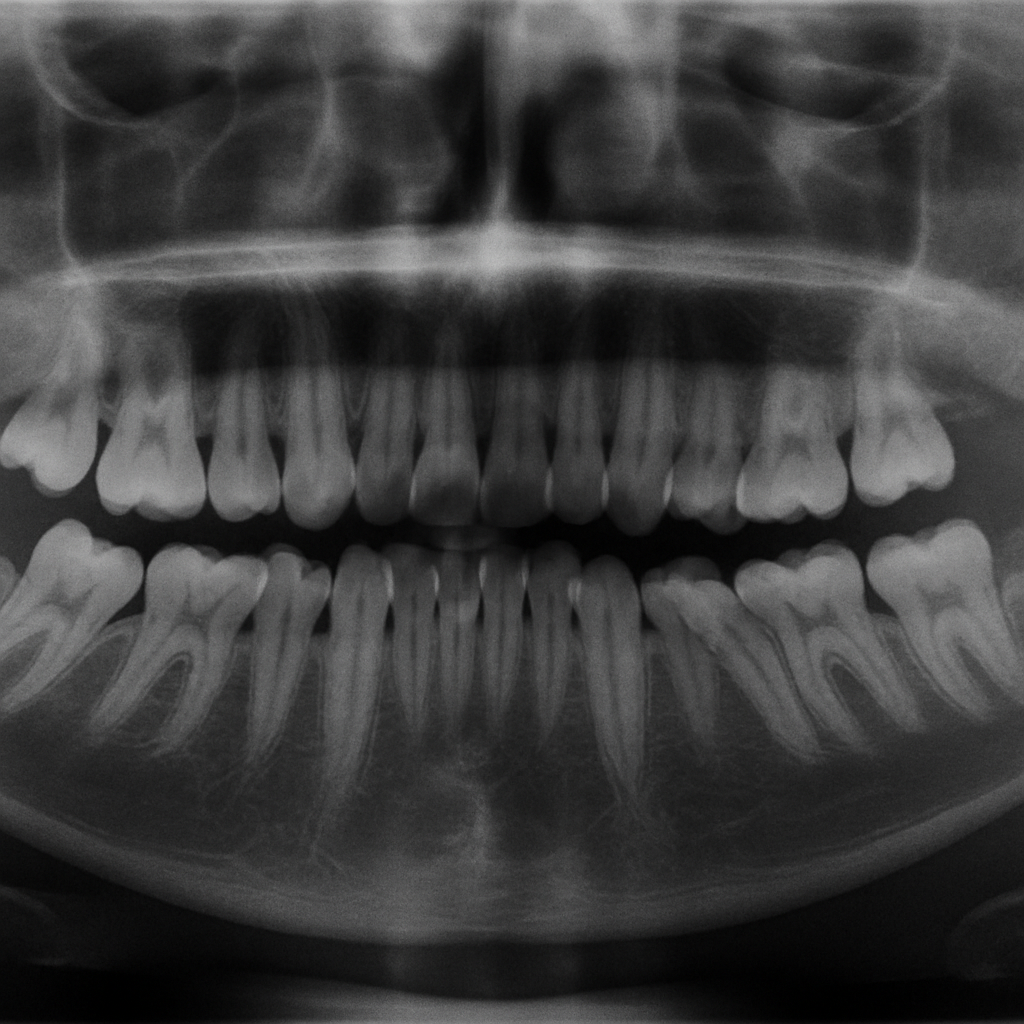

Diagnosing misaligned teeth typically involves a comprehensive dental examination. A dentist or orthodontist at the Best Dental Clinic in Manikonda will assess the alignment of the teeth and jaw through visual inspection and advanced imaging techniques such as X-rays. These assessments help determine the severity of the misalignment and identify the Best misaligned teeth treatment in Manikonda for each individual. In some cases, 3D imaging may be used to provide a more detailed view of the dental structure and guide precise treatment planning.